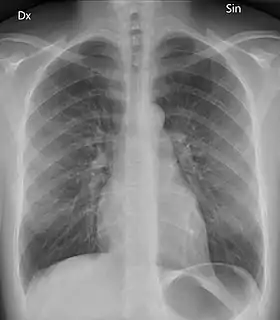

![]() A normal posteroanterior (PA) chest radiograph of someone with Interstitial Pneumonia. Dx and Sin stand for "right" and "left" respectively. | |